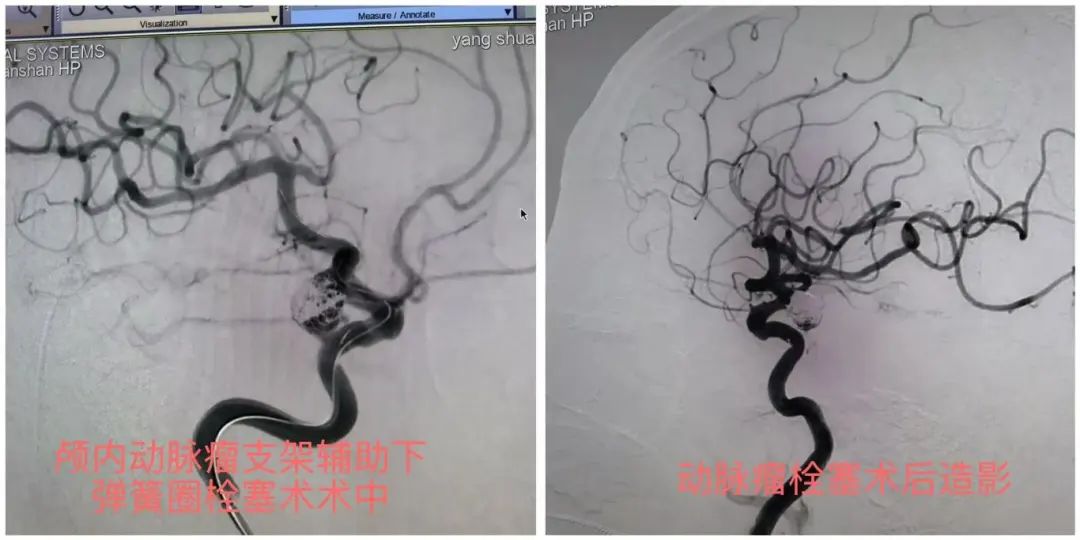

近日,一位62岁的杨阿姨(化名)因突发剧烈头疼,被家属送至铜仁市万山区人民医院,经急诊科头颅CT检查考虑为“自发性蛛网膜下腔出血”,收入医院神经外科进一步治疗。脑病中心副主任杨德昌查看患者情况后,立即组织科室医疗团队对患者病情进行讨论,结合患者症状、查体及CT检查、脑血管造影,诊断为“颅内动脉瘤破裂出血”。考虑传统开刀手术损伤大,可实施介入微创动脉瘤栓塞术,通过微创手术解决患者的大麻烦。通过与患者家属充分沟通,征求患者家属同意后,在贵州医科大学附属医院专家和杨德昌副主任的配合下,为患者成功实施了经导管颅内动脉瘤支架辅助下弹簧圈栓塞术。经过系统的术后治疗,现已康复出院。

颅内动脉瘤介入栓塞技术,是一种通过微创手术,将特制的栓塞材料(如弹簧圈、颅内支架等)精确放置于动脉瘤内部,从而阻断动脉瘤内的血流,降低动脉瘤破裂的风险。相比传统手术,介入栓塞技术具有以下优势: